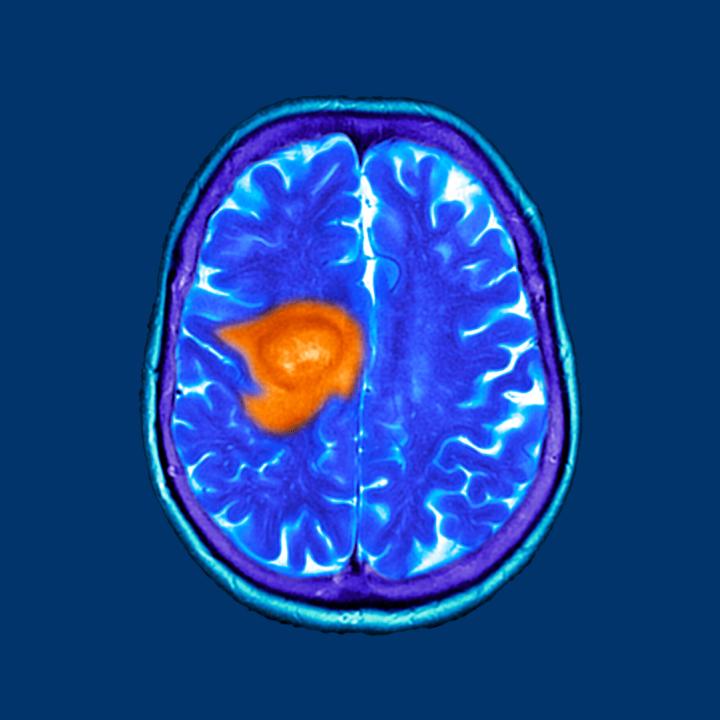

Cancerous tumors often create hypoxic (low-oxygen) environments due to their rapid growth outpacing blood supply. This lack of oxygen can make tumors more resistant to conventional therapies such as radiation and chemotherapy, which rely on oxygen to generate reactive oxygen species that damage cancer cells.